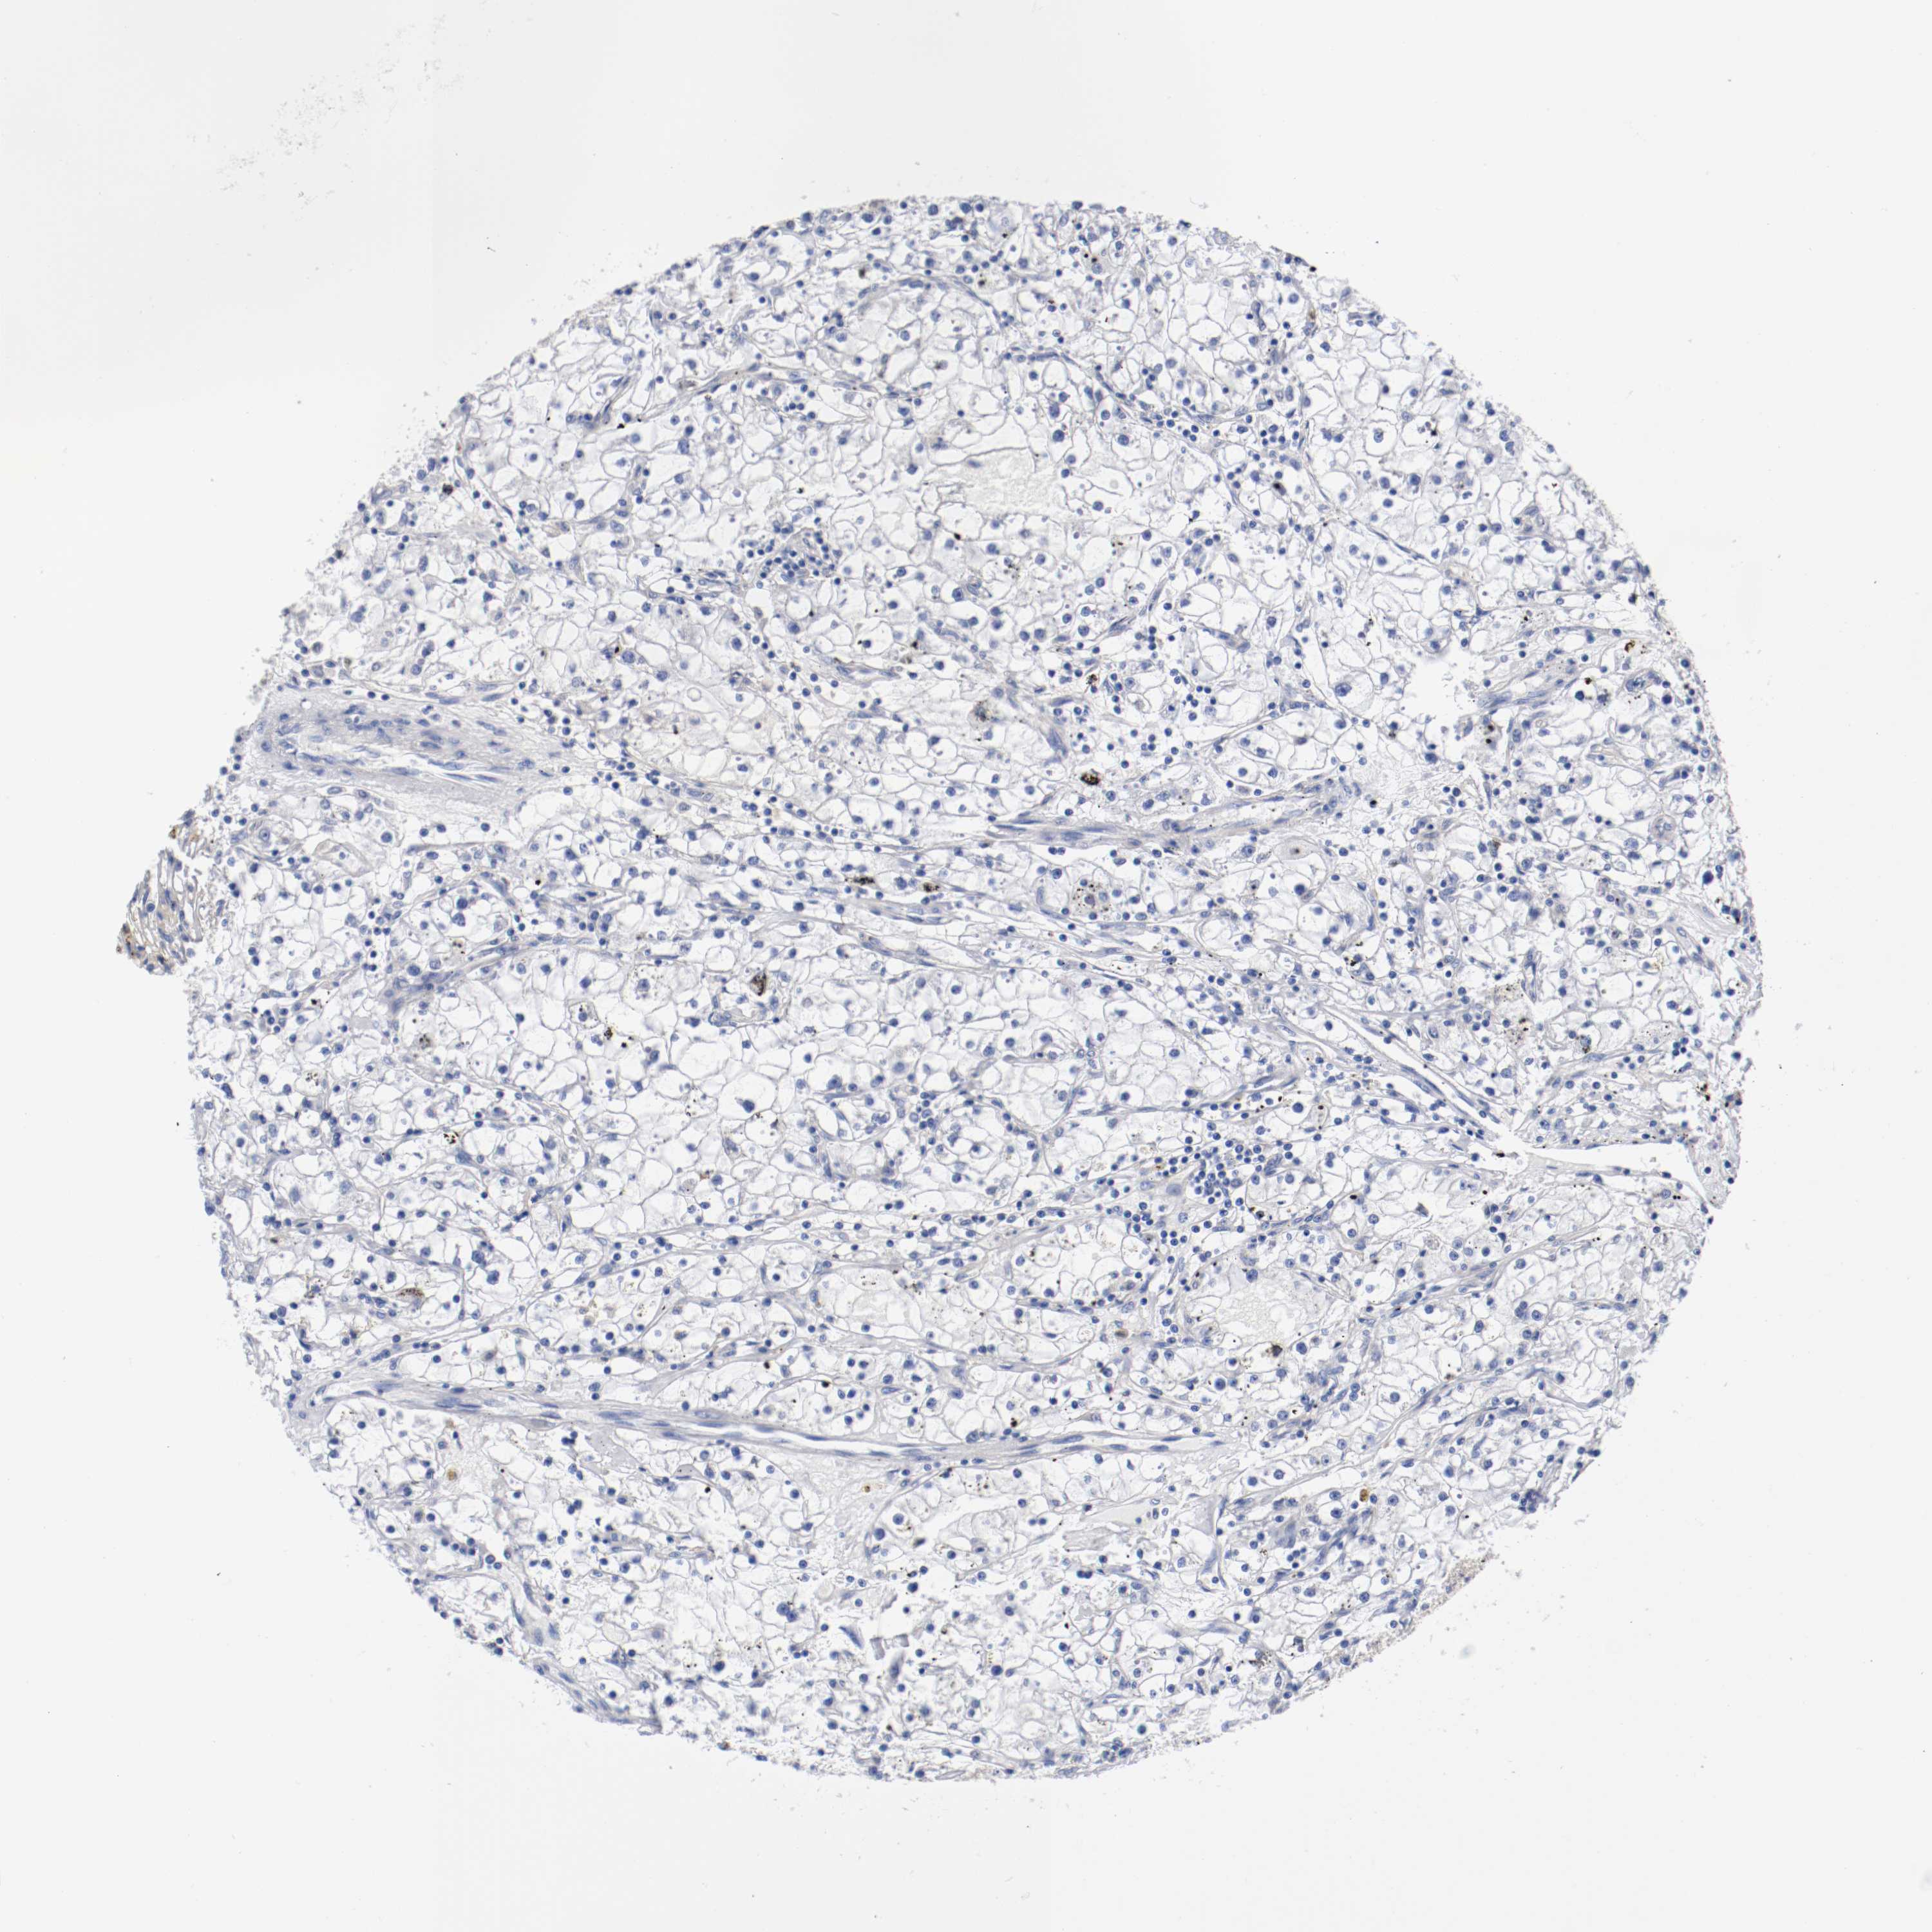

KICH TCGA KIRC TCGA KIRC VALIDATION KIRP TCGA PROTEIN RCC CPTAC PROTEIN EXPRESSION

ANTIBODIES

AND

VALIDATION